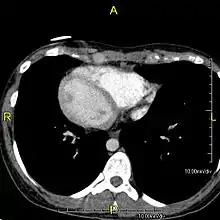

یک تصویر سیتی از قفسه سینه با دید فوقانی-تحتانی.

دید بالایی-پایینی، دید فوقانی-تحتانی، یا صفحهٔ بالایی-پایینی یا دید یا صفحهٔ آگزیال (به انگلیسی: Transverse or axial view) در پزشکی صفحه ایست افقی که بدن یا دید بدن را به قسمتهای پایینی [1] و بالایی[2] تقسیم میکند.[3]

در حقیقت این دید همان دید مقطعی است که در اکثر تصویرگیریهای سیتیاسکن دیده میشود. گاه به جای واژه "دید" در این موضوع از واژههای "برش" یا "مقطع" یا "صفحه" نیز استفاده میشود .